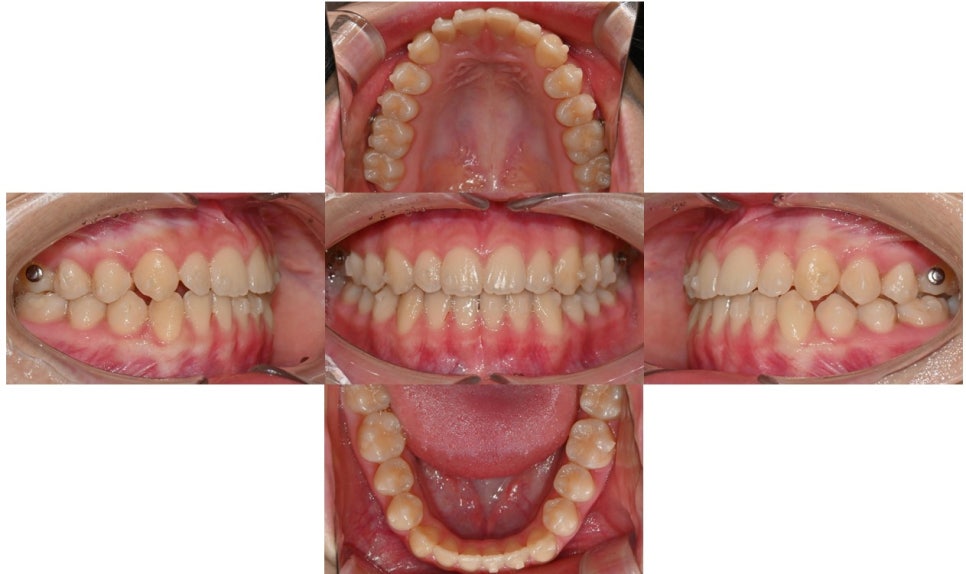

2024.8.12. 초진

초진시 위아래 앞니끼리 맞물리는 절단교합 양상을 보이고 있었으며 아래 앞니는 치아 사이가 많이 벌어져 있었습니다. Cephalometric x-ray 상 아래턱이 발달한 제 3급 부정교합 (주걱턱) 양상을 보이고 있었고, 수완부사진 성장판 검사 결과 SMI 7~8단계에 해당하여 사춘기 최대 성장기는 지난 상태였습니다.

치료 시작 2개월 후로 아래 앞니 공간이 조금씩 닫히고 있습니다. 공간이 닫히며 절단교합이었던 앞니 교합이 조금씩 개선되고 있습니다.상악 어금니들의 이동으로 어금니 교합은 살짝 떠 있는 상태입니다.

치료 시작 2개월 후